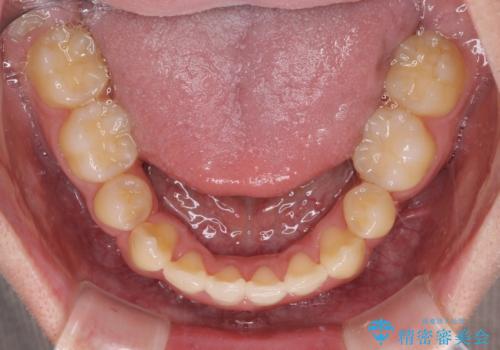

- 上下の八重歯や乱杭歯を気にして来院され患者様です。

スペースを確保するため、上下左右の小臼歯を抜歯し、ワイヤー装置に矯正することとしました。

奥歯の咬み合わせの左右差が大きかったため、変則的な抜歯矯正を行いました。

治療期間はやや長期化しましたが、満足のいく歯並びとなりました。